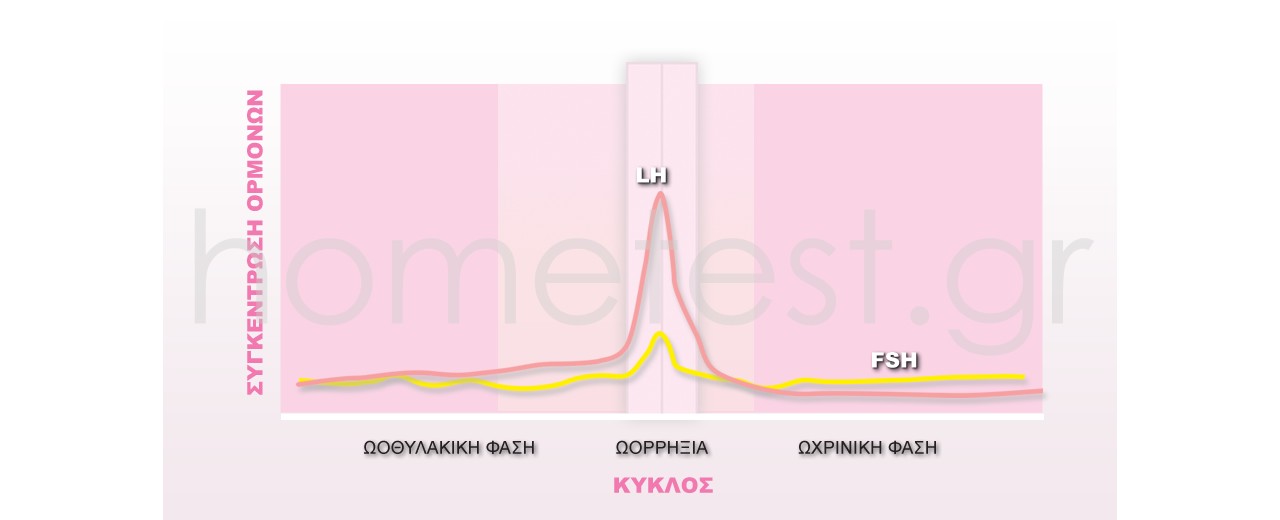

Αρχικά ο οργανισμός «ξυπνάει» τα ωοθυλάκια τα οποία βρίσκονται σε ύπνωση μέσα στην ωοθήκη. Υπενθυμίζουμε πως οι...

Ας δούμε πρώτα τι είναι η FSH.

Πριν μπούμε σε έξοδα και σε εξειδικευμένες εξετάσεις, μπορούμε να ξεκινήσουμε κάνοντας το τεστ της ορμόνης...

Πώς βρίσκω την ωορρηξία μου;

Πριν απαντήσουμε, ας κάνουμε μια σύντομη επισκόπηση της διαδικασίας της ωορρηξίας και του τρόπου που λειτουργούν τα τεστ ωορρηξίας.

Οι γυναίκες γεννιούνται με συγκεκριμένο αριθμό ωοθυλακίων τα...